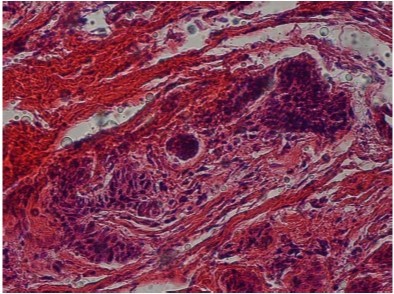

According to the microscopic analysis of the incisional biopsy of the anterior mandibular lesion extending from the mesial left canine to the right first premolar, epithelial detachment from the connective tissues was observed in some areas of the cystic structure lined with para-keratinized stratified squamous epithelium. The connective tissue of the cyst wall was fibrocollagenous with diffuse infiltrates and the inflammatory cells were mainly chronic and comprised islands of odontogenic epithelium with a marginal band of cylindrical cells resembling ameloblasts. Blood vessels, nerves, muscles, extravascular hemorrhage and hemosiderin pigment were observed. The microscopic observations confirmed the diagnosis of inflammatory odontogenic keratocysts (Figure 5 and Figure 6). The patient underwent marsupialization in the symphysis and the lateral ramus for treatment and was then followed up with for the purpose of this study for 8 months.No recurrence was seen.

Figure 6.Hematxylin-eosin staining, The odontogenic epithelium in the fibrocollagenous cyst wall